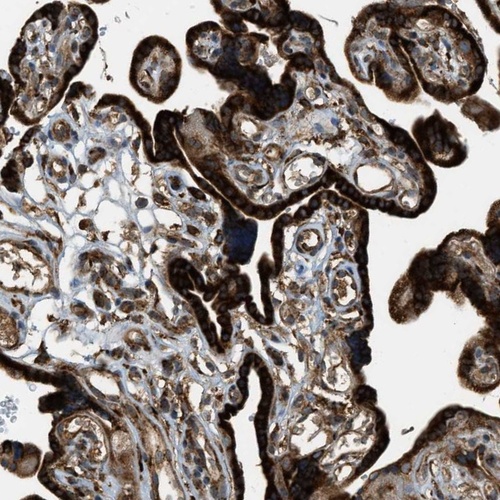

Immunohistochemical staining of human placenta shows strong cytoplasmic positivity in trophoblastic cells.